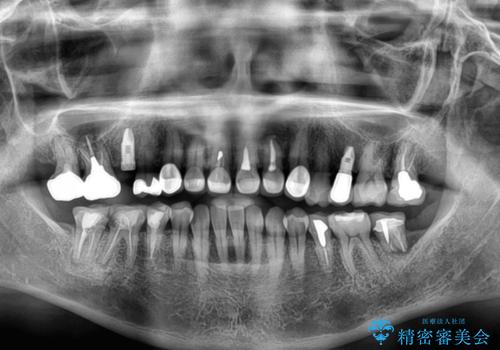

- 地元の歯科医院で治療を行っていたものの、難しいので都会に行くように指示をされたとのことで来院された患者様です。

右下のむし歯が歯肉縁下に及んでおり、歯周外科処置(歯冠長延長術)を行った上で、根管治療を行い、状態を整えて補綴治療を行うこととしました。

上顎前歯の根尖病変に痛みがありましたが、既に前歯が補綴治療済みであっため、外科的歯内療法(歯根端切除術)を行うことで解決することとしました。